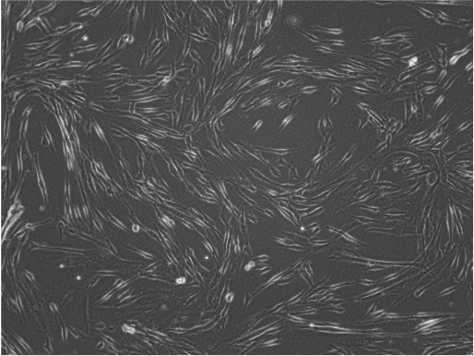

Morphology and growth characteristics

CP-MSC/TERT308 cells can be grown for a minimum of 50 population doublings with a stable growth rate and without showing signs of growth retardation. The cells are characterized by the typical spindle-shaped mesenchymal morphology.